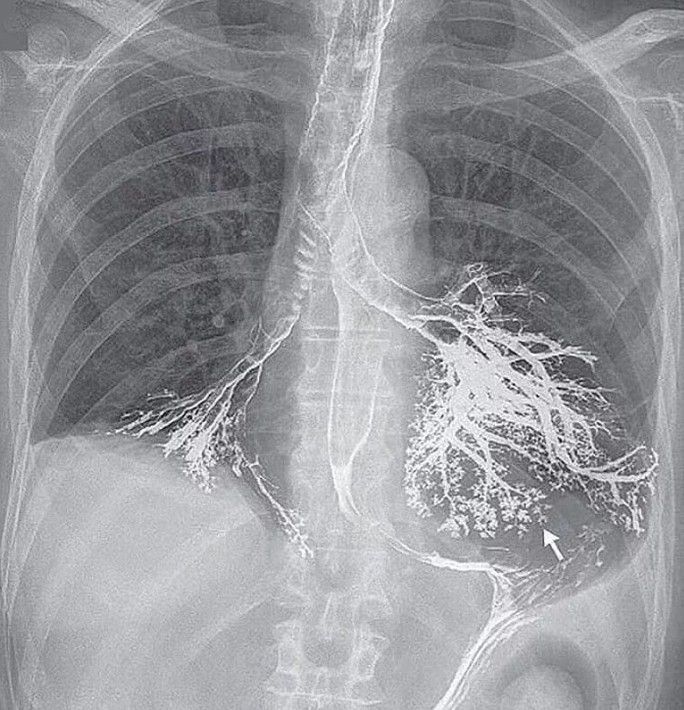

Interprete the chest X-ray

What are the likely events leading to this chest X-ray appearance.

Aspiration of barium during a swallowing video